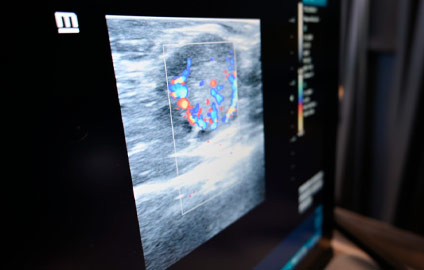

Confira algumas fotos: